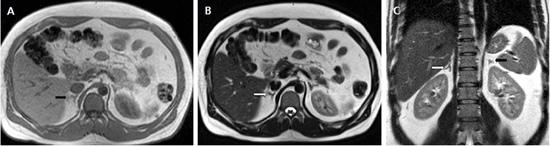

Las masas suprarrenales son un hallazgo frecuente en la población general, con una prevalencia que varía entre un 1a un 8,7% en grandes series de autopsias. Los incidentalomas se describen en aproximadamente un 4-6% de la población (Figura 4 a y b), y su prevalencia aumenta con la edad, siendo de 0,2% en pacientes entre 20 a 29 años, y de 7 a 10% en pacientes de mayor edad4. Se observan también con mayor frecuencia en pacientes obesos y diabéticos, especialmente de sexo femenino.

BLos márgenes de la lesión pueden ser una característica útil, los contornos irregulares se asocian a una mayor probabilidad de malignidad. Sin embargo, las metástasis, especialmente si son pequeñas, pueden presentar una morfología muy similar a la de un adenoma (Figura 6), vale decir homogéneas y de bordes bien delimitados. Se ha descrito también que la preservación de la morfología adreniforme usualmente se asocia a benignidad (Figura 7 a y b).

Figura 6. Lesión homogénea, de contornos bien delimitados (flecha) visualizada en tomografía computada sin contraste realizada en contexto de estudio de diseminación de cáncer mamario. A pesar de los caracteres morfológicos aparentemente benignos, se demostró que la lesión correspondía a una localización secundaria.